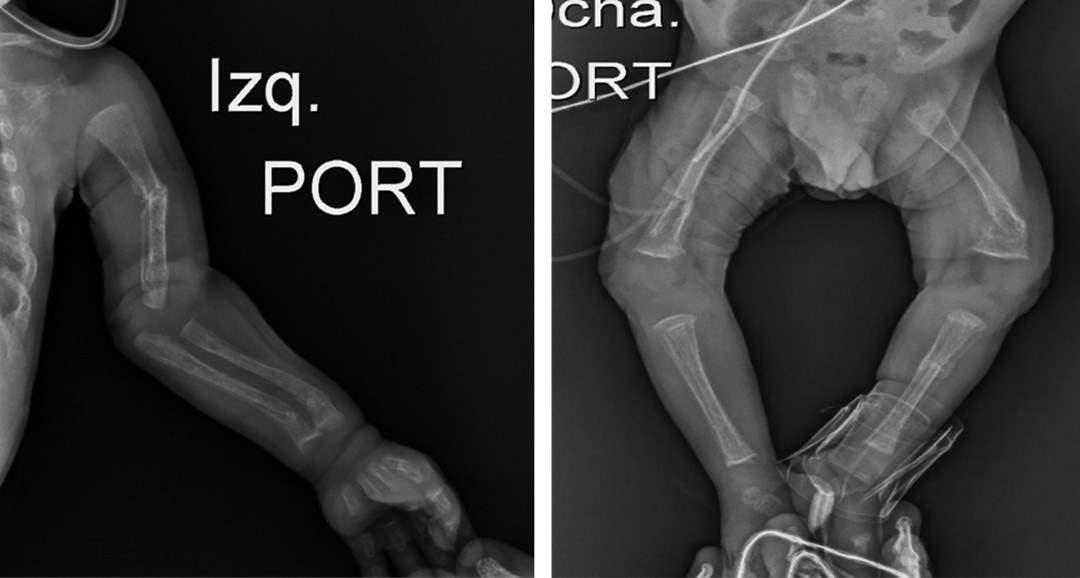

En el control ambulatorio a las 24 semanas de vida, el paciente presentaba adecuada ganancia ponderal, parámetros bioquímicos en límites normales (Tabla 1), y en las radiografías de huesos largos mostraban discreto ensanchamiento metafisario y curvatura anómalas por fracturas previas (Figura 2).